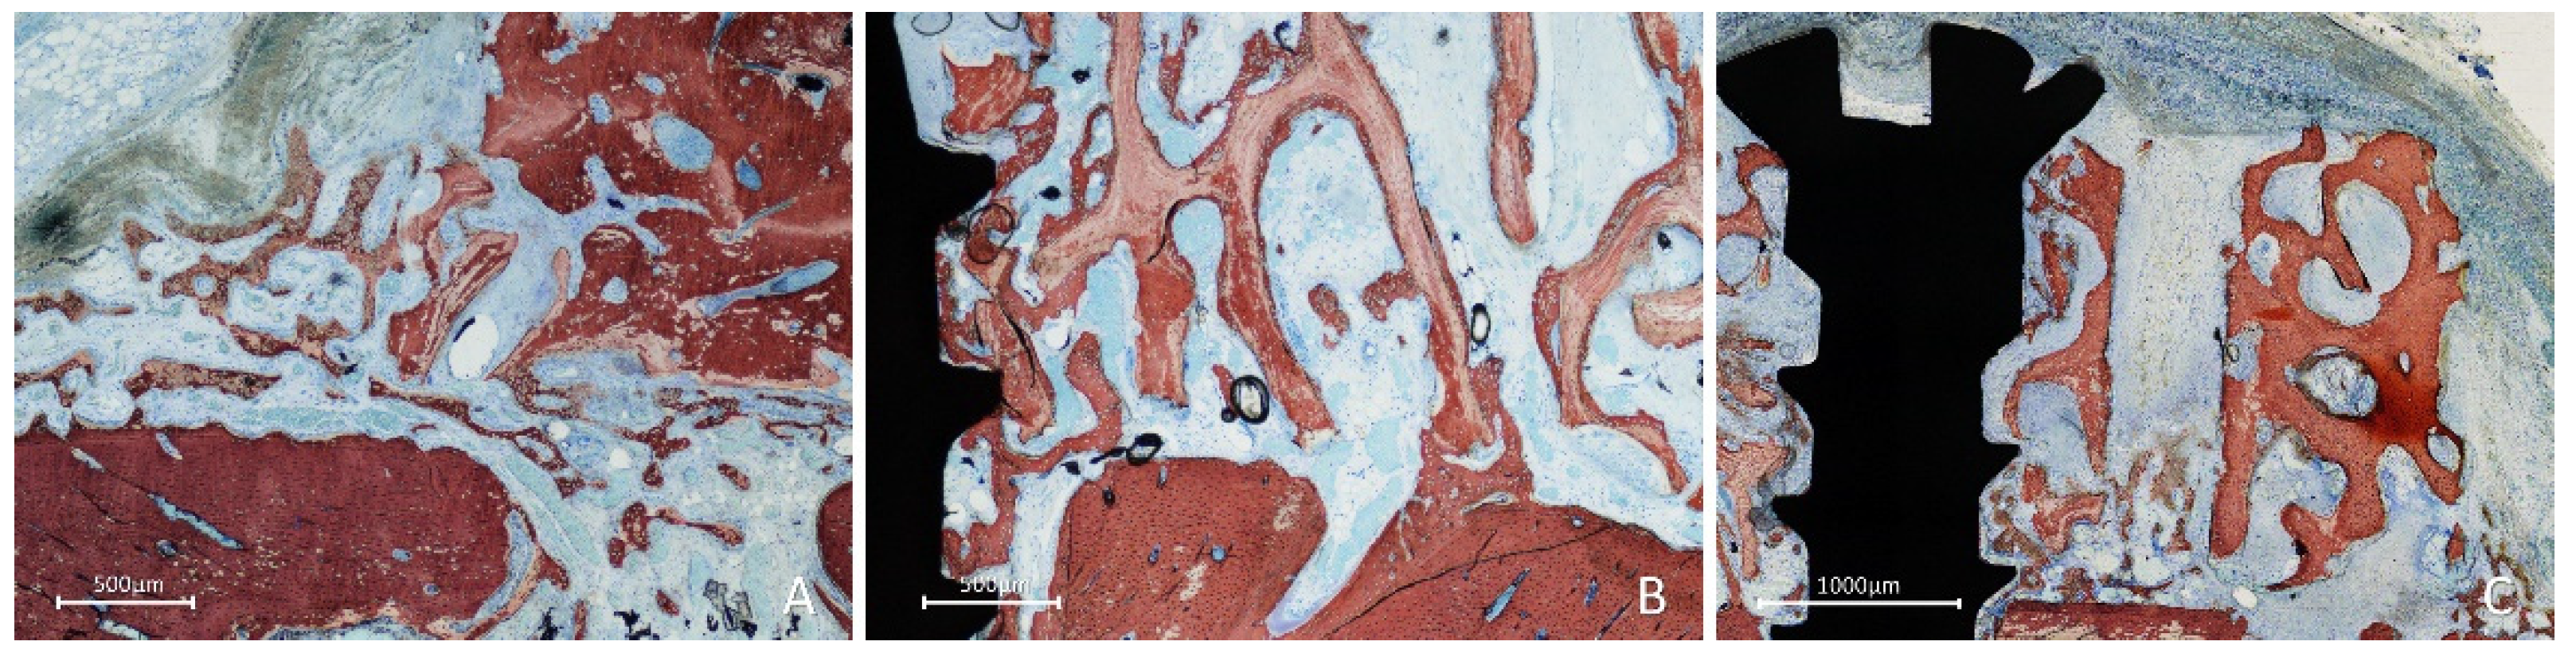

In most cases in the inlay group, the bone lined the trabeculae of the graft, and the spaces were filled with a dense provisional matrix or bone marrow (Figure 8A). In some instances, dense bone occupied a large part of the graft (Figure 8B); in several cases, the graft was covered by newly formed bone (Figure 8A,B).

Figure 8. Figure 6. Photomicrographs of ground sections showing healing aspects at inlay graft sites after 10 weeks. A, In some instances, dense bone occupied a large part of the graft. B, in several cases, the graft was covered by newly formed bone. Stevenel’s blue and alizarin red stain.